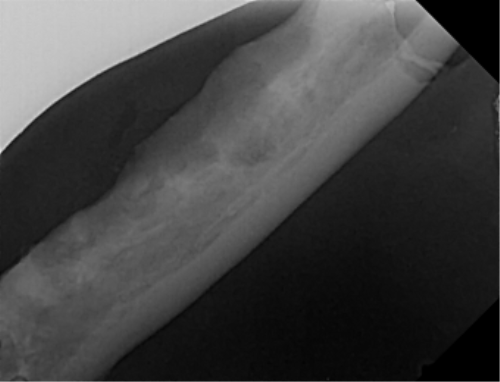

| 치료과정 | -다행히 상추는 금세 포획이 되어서 2번 시도 만에 병원으로 데려갈 수 있었습니다. -많이 마르고 구내염이 꽤 지속된 상태로 보여 검사 후 수술을 진행하기로 했습니다. 방사선, 초음파, 혈액검사를 진행했고 검사상 감사하게도 수술이 가능한 수치가 나왔습니다. 더 못 먹고 염증이 지속될 경우 건강이 더 상할 것 같아 바로 수술을 진행하였습니다. -진통 패치 및 진통제, 항생제 처방을 해주시고 먹는 것을 병원에서 관찰해주셔서 소식을 전해 들을 수 있었습니다. 아이는 첫날 조금밖에 먹지 않았으나 다음날부터 습식에 비벼 준 사료 등을 두 그릇씩 먹으며 씩씩하게 지내주었습니다. 병원 케어를 좀 더 받았으면 하여 일주일 정도 입원을 하였고 피하수액 등을 하여 탈수도 교정이 좀 되었으면 하는 심정이었습니다. -병원에서 마취 상태에서 입 안 사진을 찍어 기록한 후 보여주셨는데 꽤 심각했습니다. 목구멍 쪽 증식한 염증을 많이 절제하였고 레이저 치료까지 진행하였습니다. 치아 엑스레이 촬영도 모두 보내주셔서 기록해두는 데 도움이 되었습니다. -아이가 자발 식이를 잘 할 경우 퇴원을 해도 되기에 집에서 회복 공간을 만들어주었습니다. 나가고 싶은 듯 바깥을 보며 처음에 힘들어했지만 점차 적응하며 편안하게 휴식을 했습니다. 밥은 꼬박꼬박 두 그릇 넘게 챙겨 먹었고 소화가 잘 되는 습식 위주로 주었습니다. 건사료를 언제쯤 먹을 수 있나 관찰하려 두었더니 며칠 안에 금세 먹었습니다. 알갱이 작은 사료를 주었으나 기존에 먹던 맛을 먹고 싶은지 그것만 먹었습니다. |

| 대상묘 치료중 사진 |          |